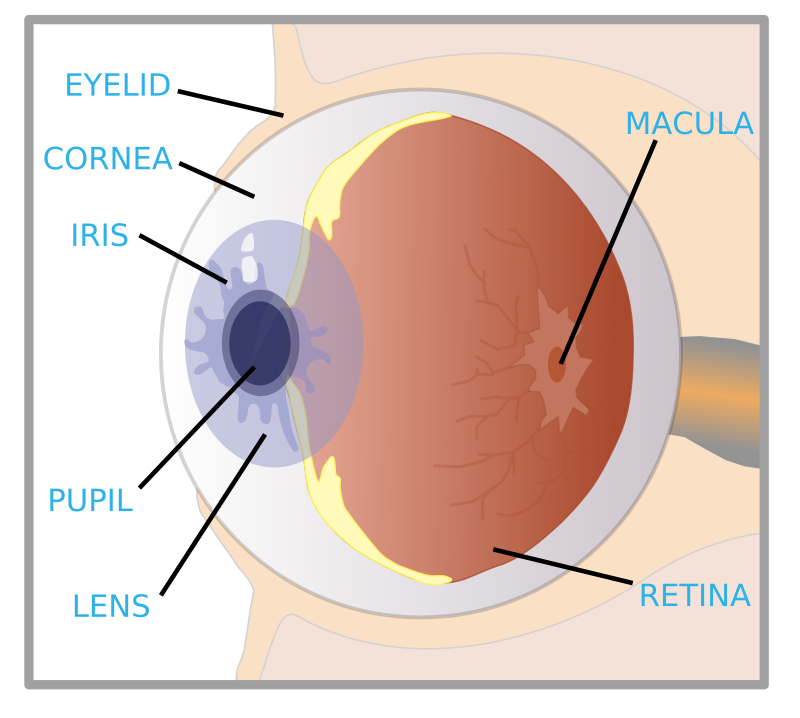

Biology-How our eyes work – Howthingswork.org

CBSE Papers, Questions, Answers, MCQ …: CBSE Class 10 – Physics …

vision and the eye (lesson 1063) – TQA explorer

Lab 35: Eye Structure Flashcards | Quizlet